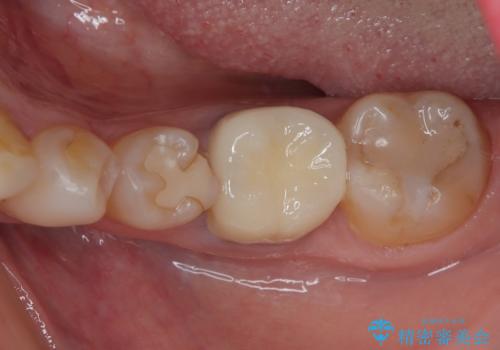

インプラント治療をきっかけに、銀歯を全てセラミックに替えていきました。

人の目を気にせずに、大きく口を開けて笑えるようになりました。